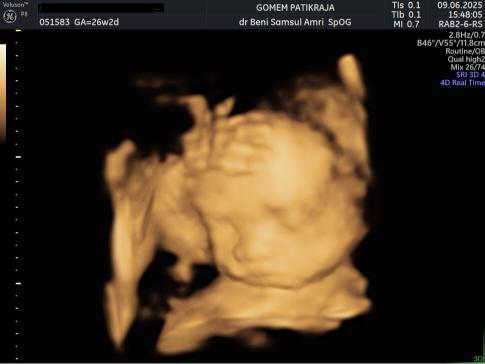

USG Janin 26 Minggu

Matangnya sistem kekebalan tubuh janin menjadi fokus utama di tahap ini. Ia sudah memiliki pola pernapasan yang lebih teratur meski masih di dalam air ketuban. Ukuran kepalanya sudah proporsional dengan badannya.

Matanya sudah mulai membuka dan menutup secara berkala. Pastikan lingkungan sekitar ibu tetap tenang dan nyaman untuk kesejahteraan janin.